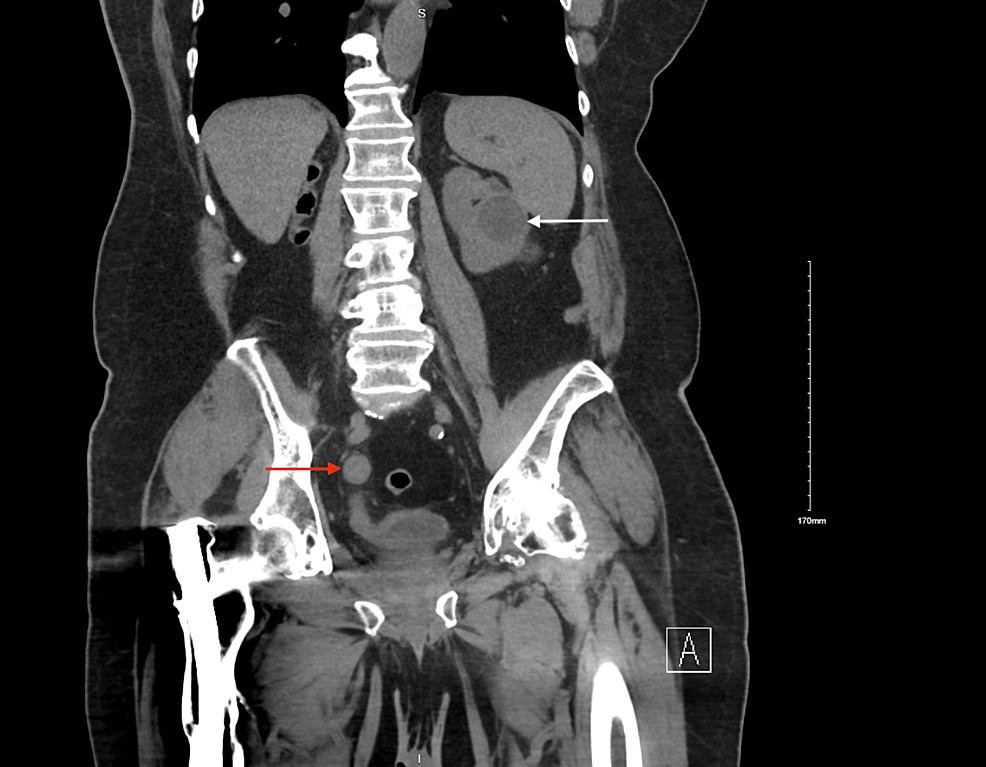

From www.researchgate.net

CT scan images showing the ureteric stump tumor Download Scientific What Is A Stump Tumor benign uterine leiomyomas, or smooth muscle tumors (smt), are neoplasms of the myometrial layer of the uterus and are the most common tumor in pelvic. the term smooth uterine muscle of uncertain malignant potential (stumps) indicates a group of uterine. a stump can be defined as a uterine smooth muscle cancer that cannot be diagnosed unequivocally as. What Is A Stump Tumor.

CT scan images showing the ureteric stump tumor Download Scientific What Is A Stump Tumor a stump can be defined as a uterine smooth muscle cancer that cannot be diagnosed unequivocally as benign or. benign uterine leiomyomas, or smooth muscle tumors (smt), are neoplasms of the myometrial layer of the uterus and are the most common tumor in pelvic. uterine stump is a rare neoplasm with heterogeneous histologic findings and diverse clinical. What Is A Stump Tumor.